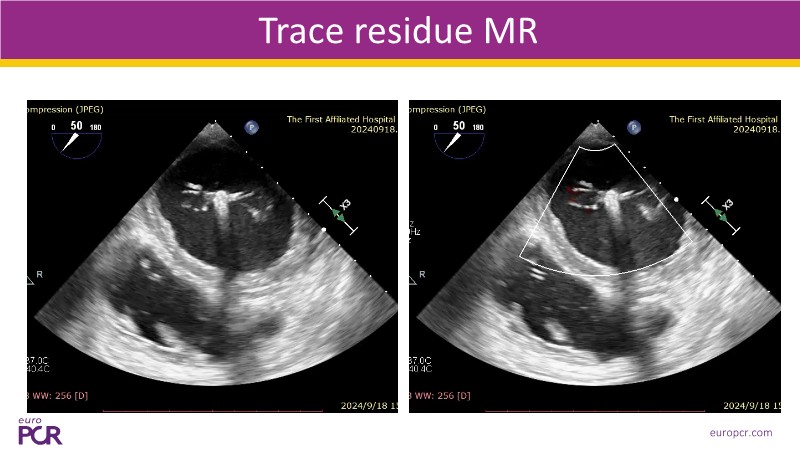

- To discover tips and techniques for mitral TEER in patients with challenging anatomy and difficult imaging